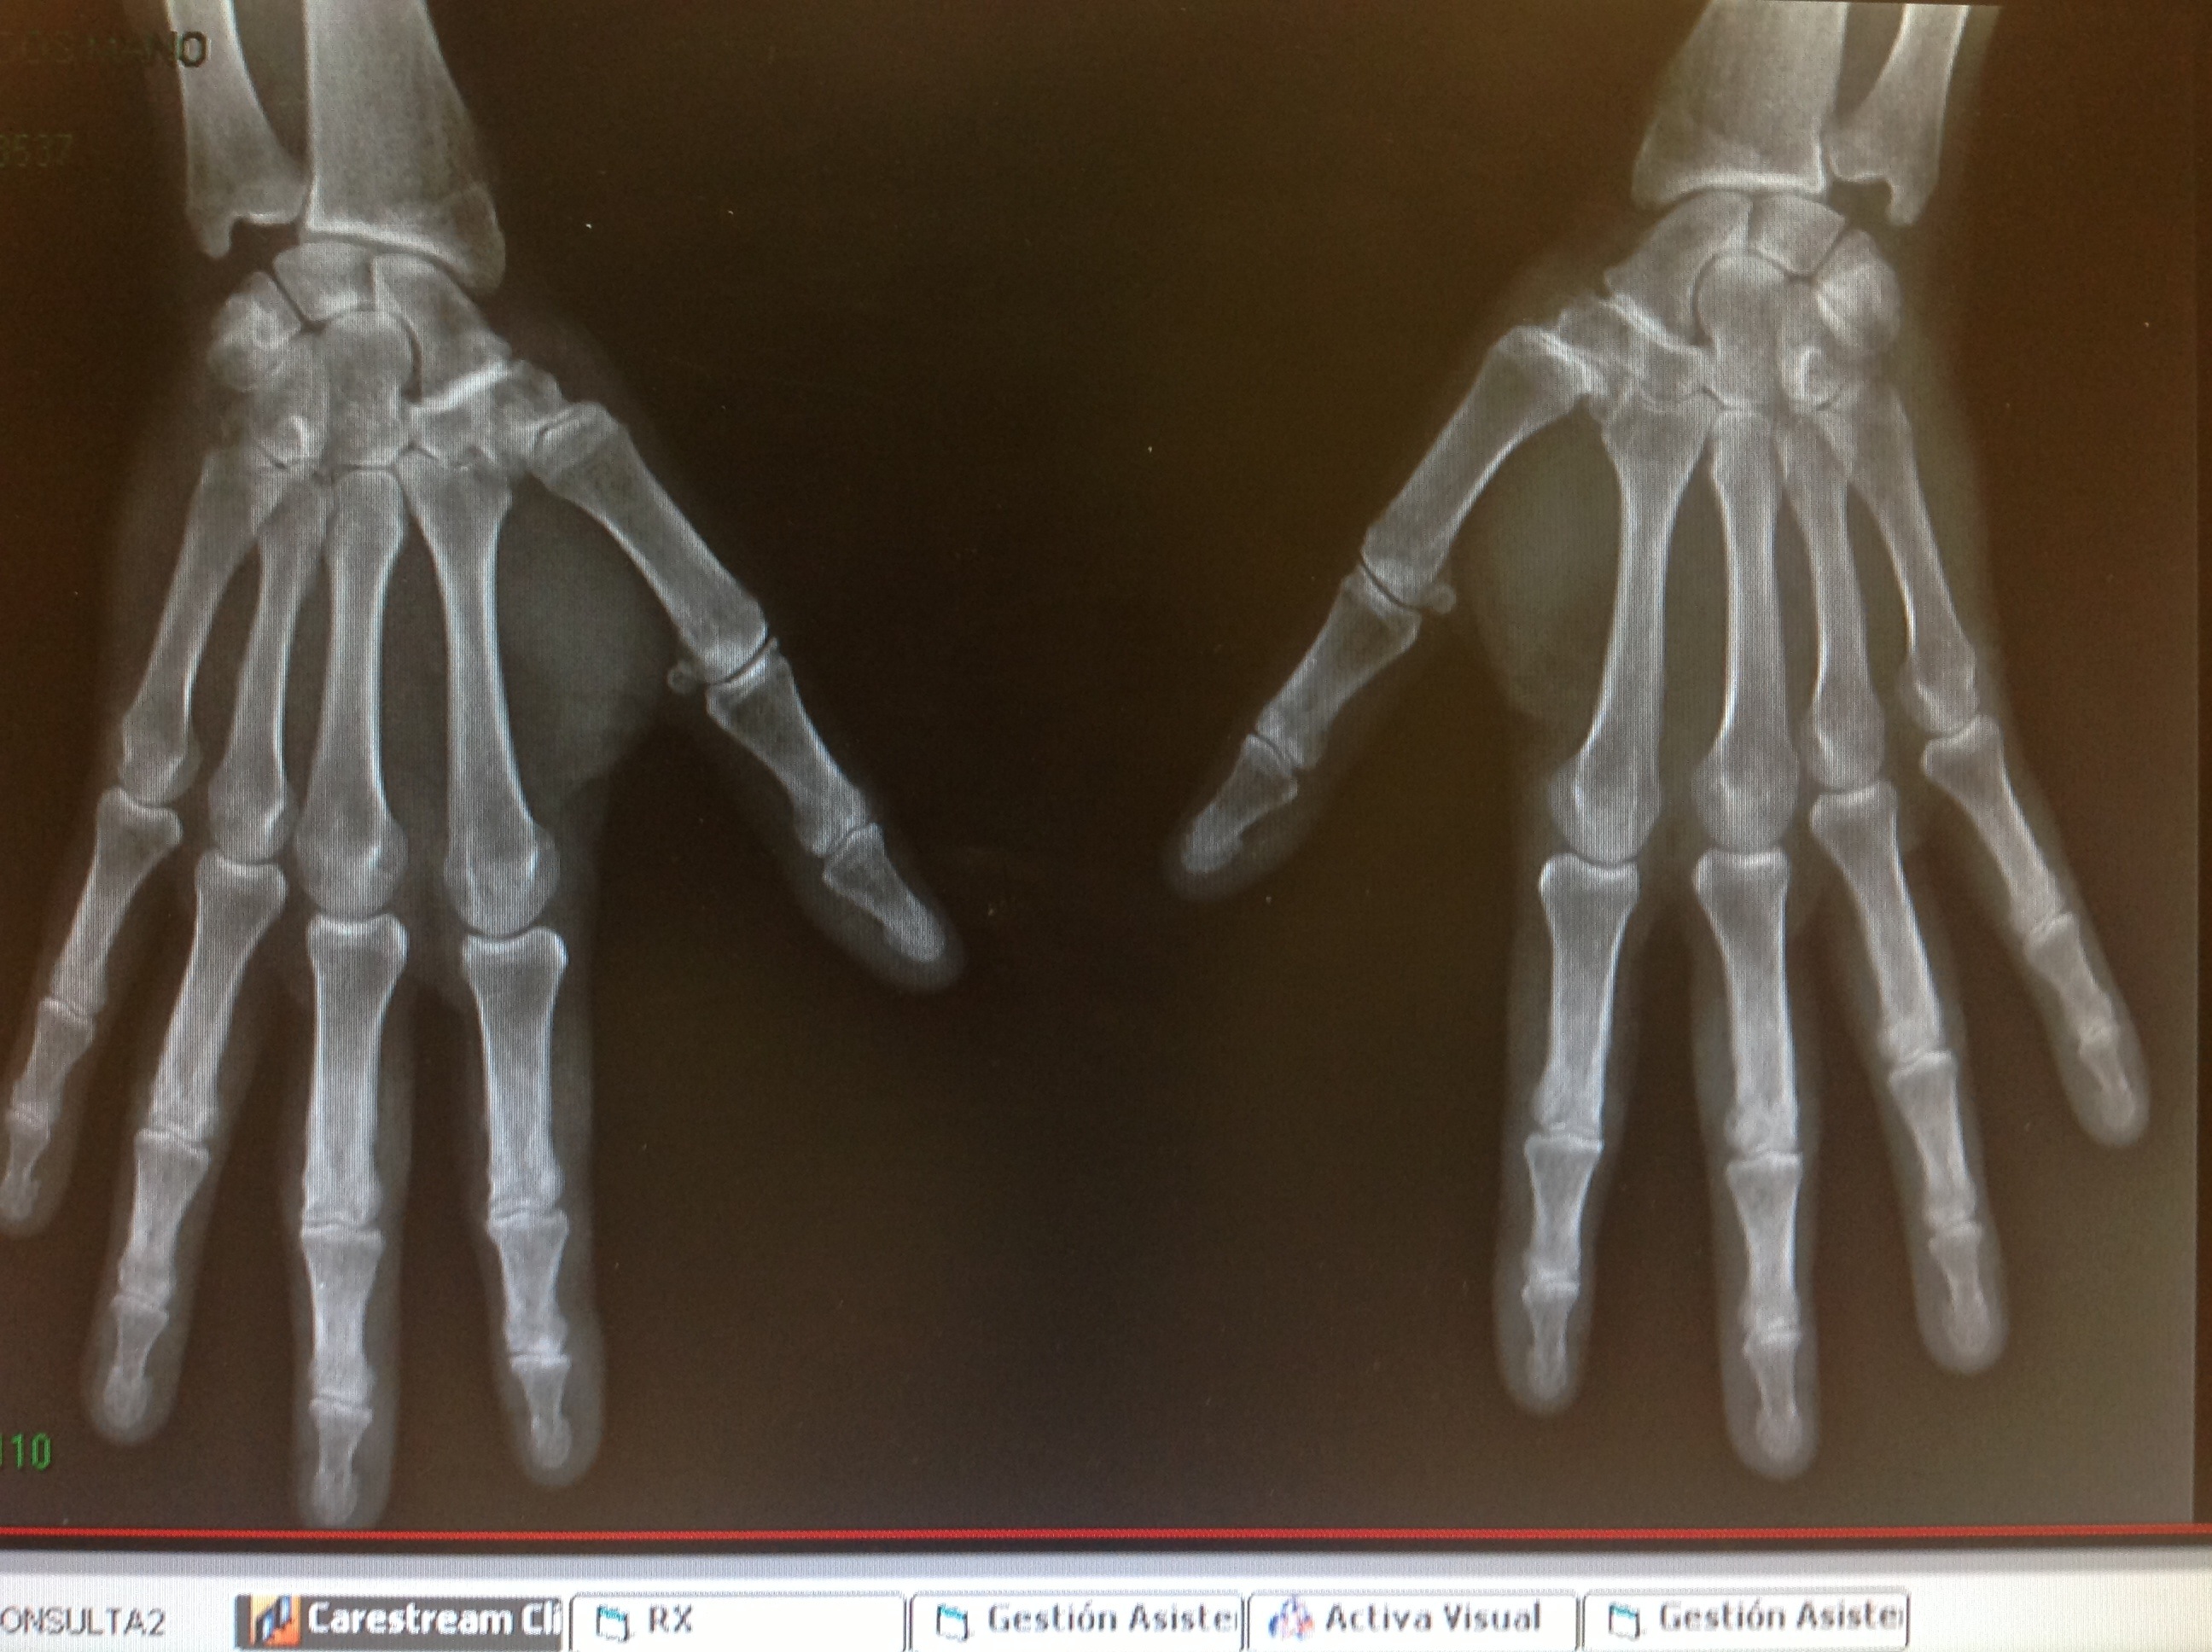

El origen más frecuente de dolor en la base de la columna del pulgar es la Rizartrosis. La rizartrosis es la artropatía degenerativa de la articulación trapeciometacarpiana. Se classifica en 4 grados según los hallazgos radiológicos ( ver el post sobre Cómo realizar proyecciones radiológicas correctas de la base del pulgar).

Pero el dolor mecánico en la base del pulgar también puede tener su origen en la articulación escafotrapeciotrapezoidea. En este caso el dolor es más proximal , justo a nivel del borde donde se inicia el reborde de la eminencia tenar. El dolor se exacerba con la extensión de la muñeca asociada a desviación radial ( por ejemplo al hacer apoyo sobre las manos para levantarse del sofá).No es infrecuente que la paciente tenga historia de ganglión volar del carpo paraarterial radial.

A menudo pueden asociarse ambas:rizartrosis con artropatía escafotrapeciotrapezoidea. Se denomina entonces artropatía peritrapecial. Debe valorarse siempre su presencia antes de iniciar el tratamiento de una rizartrosis pues éste será Diferente.